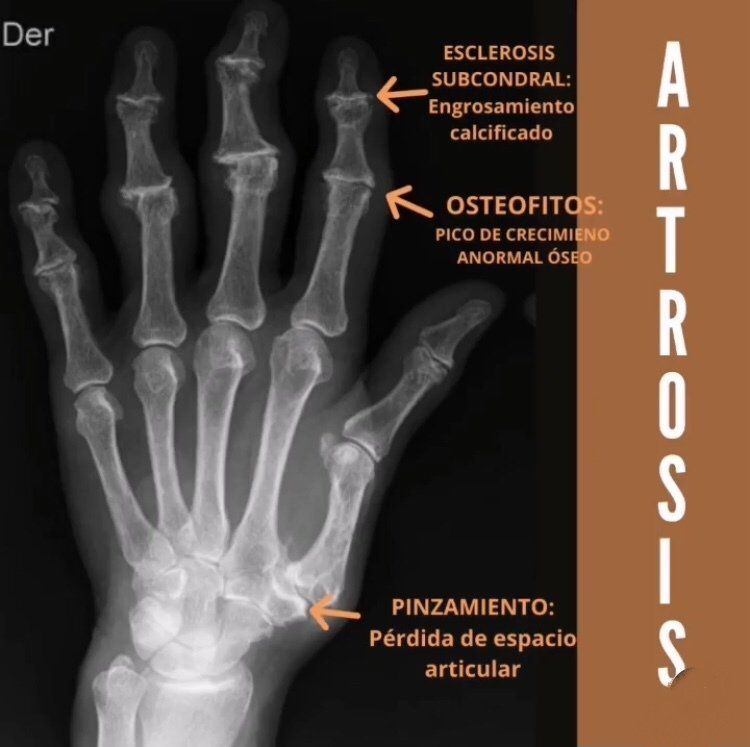

MANO CON ARTROSIS

En esta foto se aprecia la deformidad articular típica de la ARTROSIS; los NÓDULOS DE BOUCHARD en la articulaciónes interfalángicas proximales (en este caso la persona de la foto presenta más deformidad (N Bouchard) en 2 de los dedos pero puede darse en cualquiera de las 5 articulaciones IF proximales).

También se observan los NÓDULOS DE HEBERDEN que se hallan en las interfalágicas distales.

En esta radiografía se observa la subluxación provocada por la deformidad articular en la metatarsofalángica del pulgar y el desplazamiento de eje del primer metacarpiano (pulgar) en relación al hueso trapecio del conjunto óseo del carpo.

Esta última deformidad en la articulación descrita (trapecio-metacarpiana) genera mucho dolor en su fase inflamatoria cuando la persona se dispone a hacer la pinza con el pulgar, por ejemplo, cuando quiere introducir y girar la llave en la cerradura.

Si comparamos la radiografía de una mano normal (presentada anteriormente) se verá con más claridad las diferencias en relación a la mano artrósica, como la pérdida de espacio interarticular, la esclerosis subcondral (ese engrosamiento más blanco y deformado entre las uniones óseas) y los osteofitos (las defomidades óseas en forma de "pico de loro" comúnmente llamado.